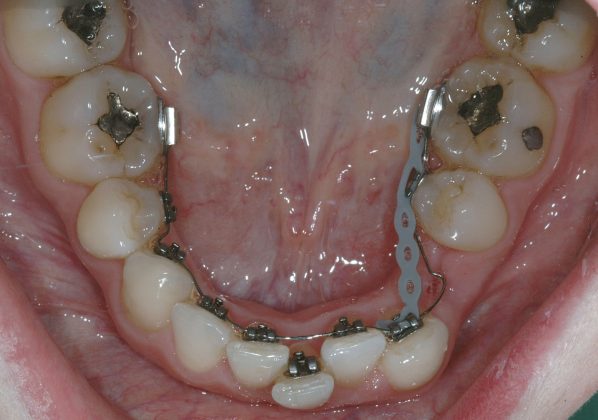

Una paziente di sesso femminile, 38 anni, già trattata ortodonticamente presso altra sede con apparecchiatura fissa a entrambe le arcate in età adolescenziale senza successiva applicazione di alcuna contenzione, si presenta alla nostra attenzione perché insoddisfatta dell’estetica del sorriso; richiede una valutazione per un trattamento ortodontico con apparecchiatura fissa linguale per la presenza di affollamento dentale a entrambe le arcate e difficoltà a mantenere una adeguata igiene orale; si riscontrano agenesia di entrambi gli incisivi laterali superiori (1.2 e 2.2) e del secondo premolare inferiore destro (4.5). Presentiamo la risoluzione del caso mediante trattamento ortodontico estrattivo a entrambe le arcate, eseguito con apparecchiatura linguale invisibile 2D e meccanica asimmetrica e seguito a medio termine da riabilitazione implanto-protesica e contenzione fissa.

Per formulare corretta diagnosi e piano di cura, lo studio del caso ha previsto la raccolta di documentazione completa standard, ovvero fotografie del viso e intraorali (Figure 1a-e), radiografia panoramica e teleradiografia del cranio in proiezione laterale (Figure 2a-b) per la relativa analisi cefalometrica e modelli di studio.

La valutazione clinica e gli esami effettuati confermano la presenza di agenesia degli incisivi laterali superiori (1.2 e 2.2) e del secondo premolare inferiore destro (4.5).

L’analisi ortodontica e la valutazione parodontale, con particolare riferimento alla posizione della radice del canino superiore destro (1.3), distoinclinata e trasposta alla radice del primo premolare (1.4) come evidente dalla radiografia panoramica e dalle immagini intraorali, ci hanno guidati nella programmazione di un trattamento estrattivo asimmetrico a entrambe le arcate.

Il protocollo terapeutico ha previsto l’estrazione del primo premolare inferiore sinistro (3.4) e del primo superiore destro (1.4), l’applicazione di una apparecchiatura fissa linguale 2D e di una meccanica asimmetrica di ancoraggio e movimento ortodontico a entrambe le arcate (Figure 3a-b).